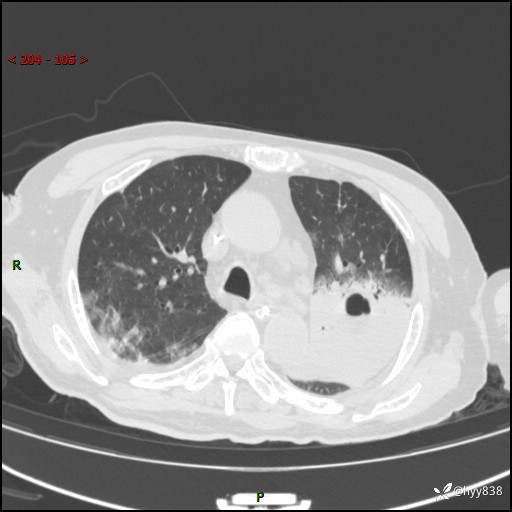

胸部CT复查(2024.8.5)